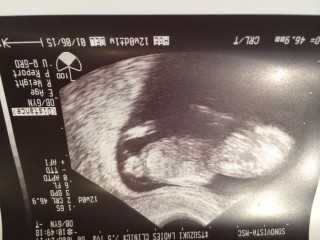

エコー写真

顔

• おなまえなつ

• ねんれい22

• 妊娠週12w0d

3週間ぶりの検診。 足先までくっきり見えました! 思わず「人間だ!」と言ってしまいました。笑 パパに似て長い足かな?♪ たくさんキックして、 元気に動き回っていました。 胎動が感じられる日が楽しみです♪